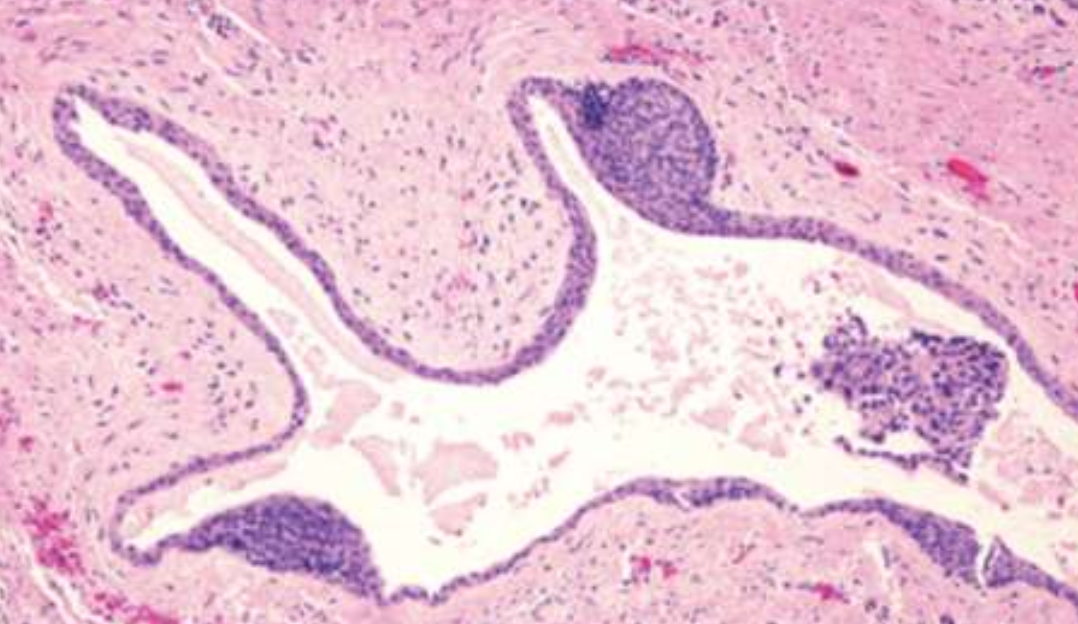

| Botryoid Odontogenic Cyst (BOC) | 多囊 LPC | ||||

| Glandular Odontogenic Cyst (GOC) | - | 下顎前牙 | 46-51y | 跨中線、無 MAML2 | |

復發、局部侵犯性,吃 cortical bone  |

|||||

| 杯狀細胞, cilia, focal plaques | |||||